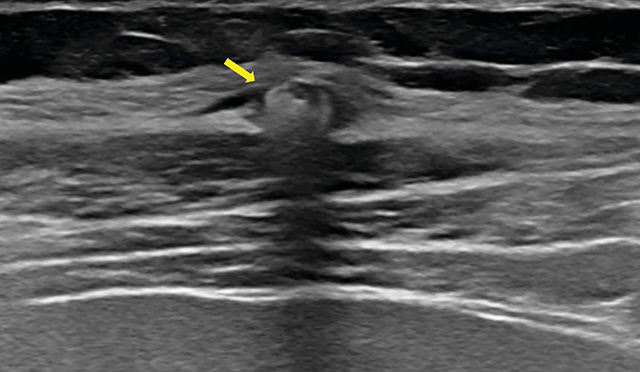

Teaching point: Twiddler's syndrome is a very rare but potentially disastrous complication after implantation of a neurostimulator or pacemaker, caused by twisting of the generator within the subcutaneous pocket, resulting in dislodgement and/or interruption of the electrodes that should be reported on x-ray.